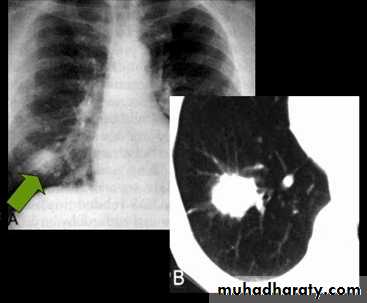

Nodular (coin) lesion in the left upper lung with irregular edge (most probably cancinoma

chest practice